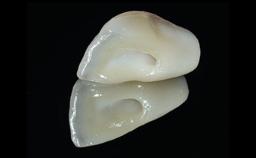

Replacement of a Failing Restored Upper Right Central Incisor, Ridge Preservation and Early Placement of an RC Bone Level Implant

A 23-year-old female, healthy and non-smoking patient had had tooth 11 temporarily restored following a trauma in adolescence. As the patient’s growth had since come to an end and the crown had fractured, she requested an implant-supported restoration of tooth 11. Moreover, the contralateral tooth 21 presented an old composite restoration at the mesial incisal edge. The periodontal tissues were healthy with periodontal probing depth values below 3 mm, but some inflammation was observed around the semi-submerged root of tooth 11.